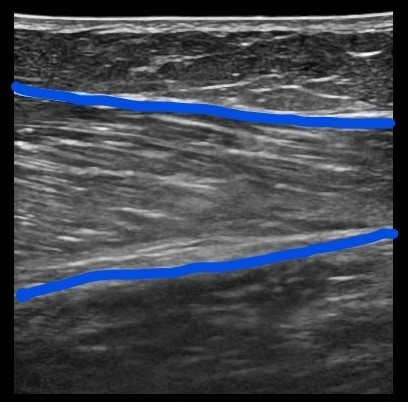

超音波診断装置を用い筋組織に炎症、損傷が生じているか画像所見を用い診断しています。下の画像はふくらはぎを撮像したものです。左は正常な筋繊維です。右は肉離れの状態です。

★正常な筋繊維の場合、筋配列がきれいに見えます。